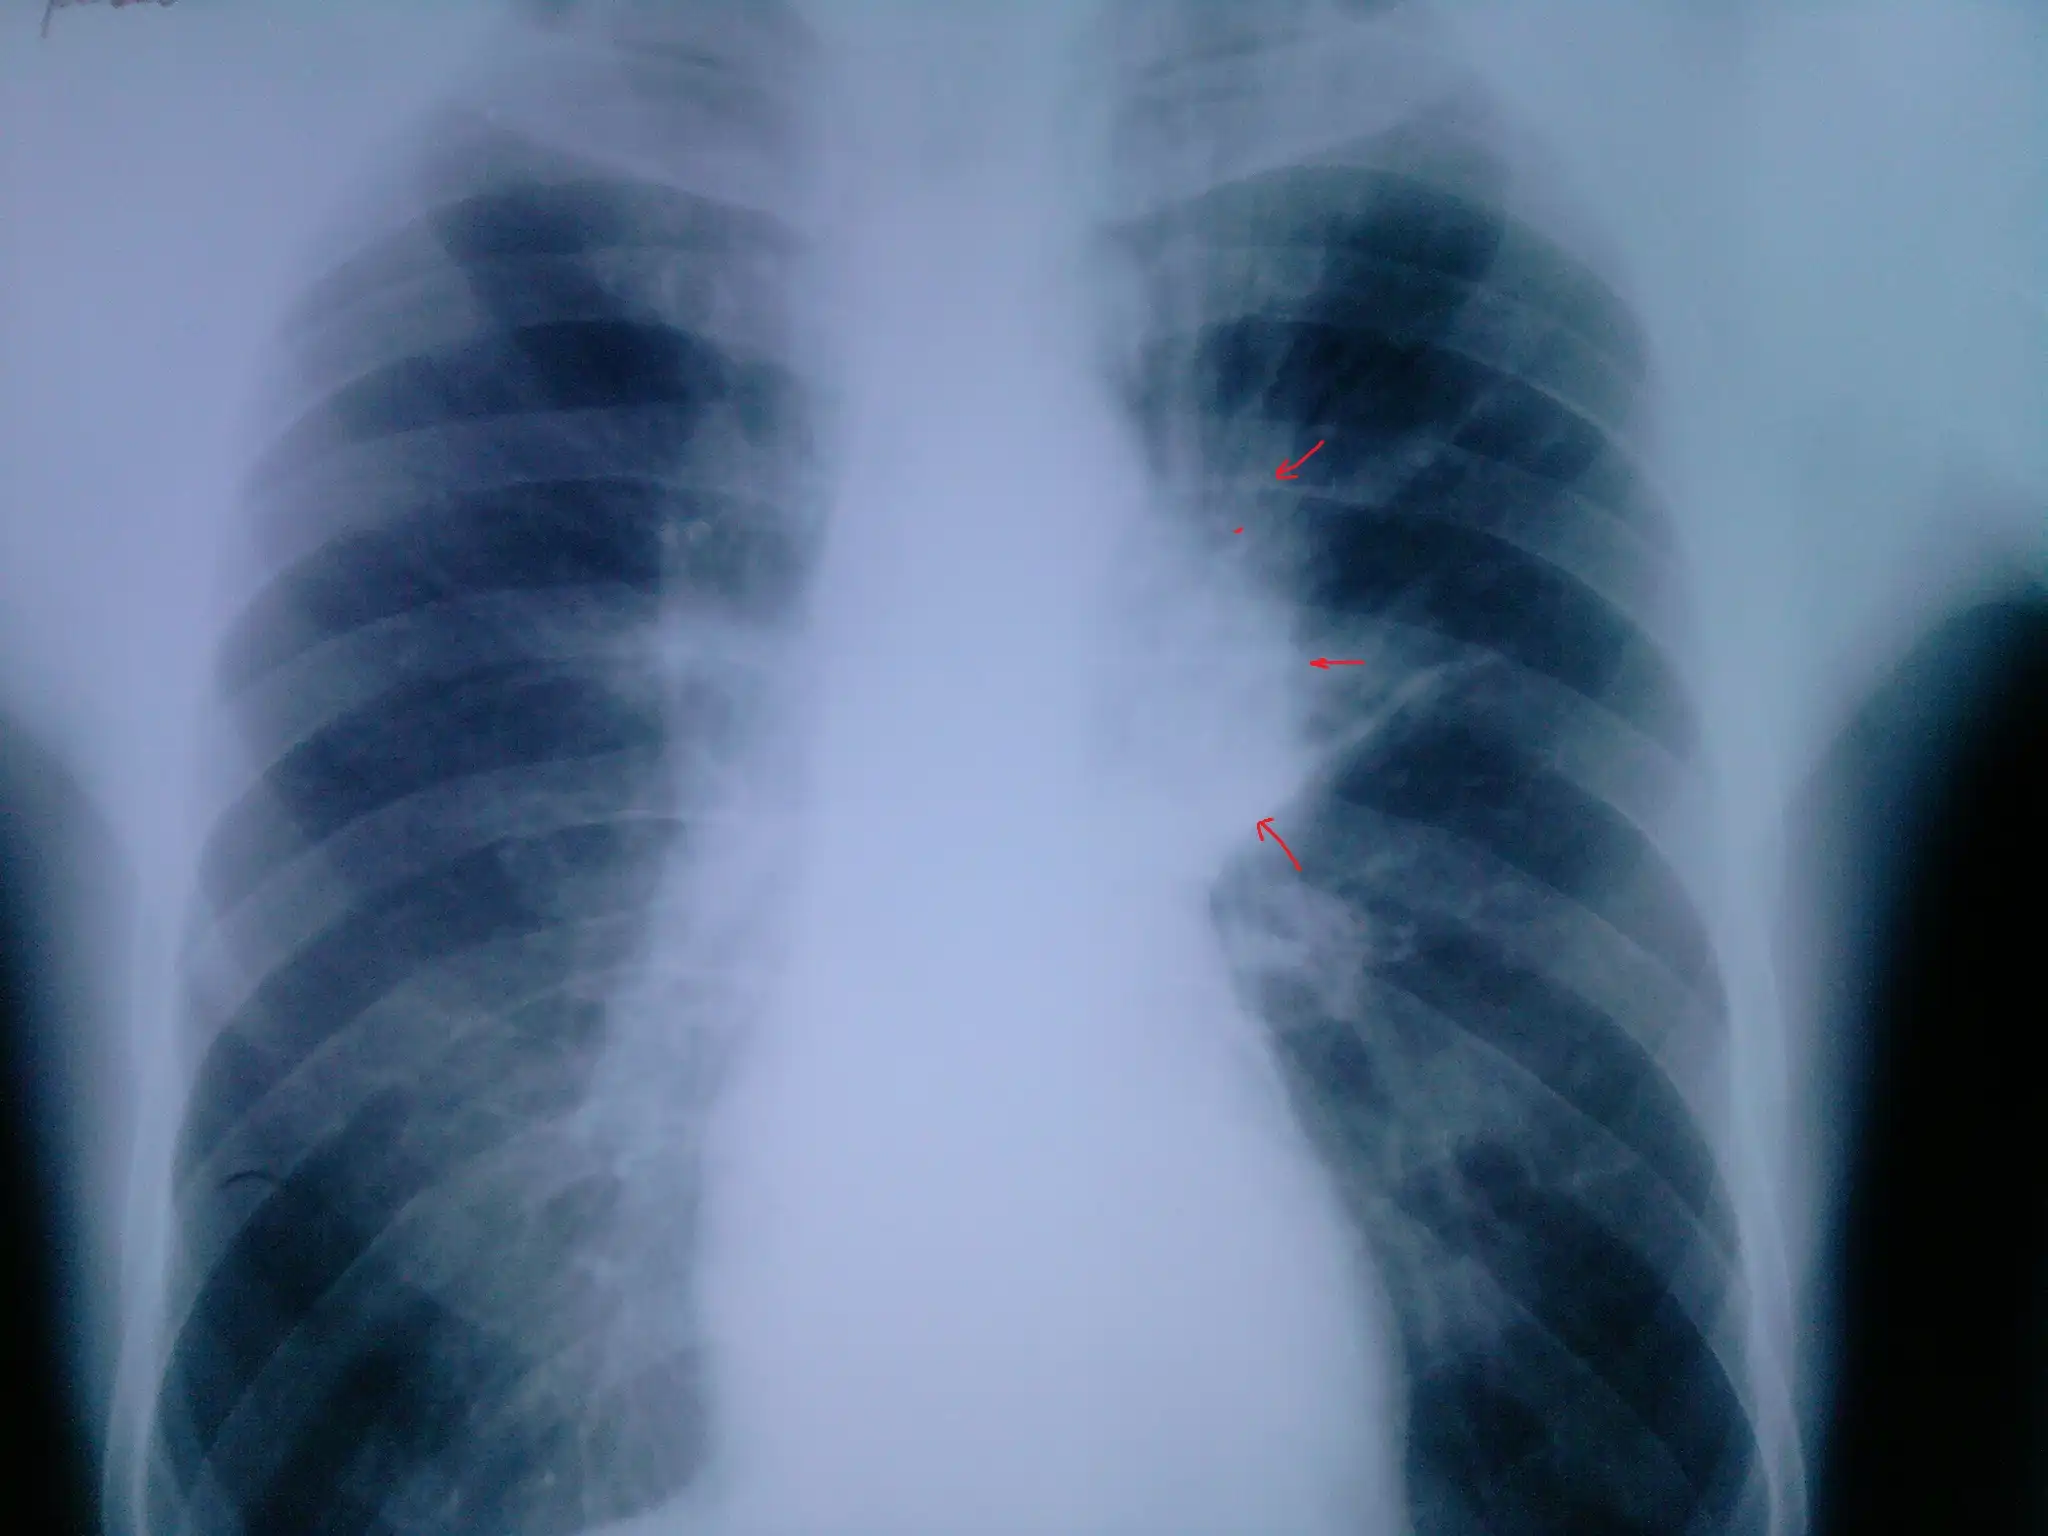

Пациент № 3:

Линейная томограмма: